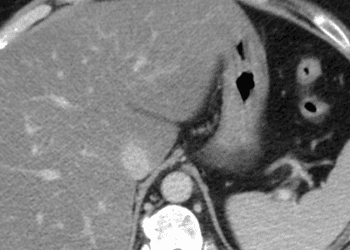

Ampullary adenocarcinoma, arising at the ampulla of Vater in the duodenum, is a gastrointestinal malignancy often treated with surgical resection with curative intent. However, the histopathologic characteristics of the resected tumor that may help predict the course of the disease are unknown. This retrospective cohort study enrolled patients who underwent pancreatoduodenectomy with curative intent for ampullary adenocarcinoma (n=887) to define histopathologic characteristics that independently predict overall survival and disease-free survival in this patient population. The median overall survival was 64 months. Researchers found that independent predictors of overall survival included adjuvant chemotherapy, which improved overall survival (HR 0.69, 95% CI 0.48 to 0.97), N-stage (HR 3.30, 95% CI 2.09 to 5.21) and perineural invasion (HR 1.50, 95% CI 1.01 to 2.23) were also both independently associated with lower overall survival. N-stage was also an independent adverse predictor for disease-free survival (HR 2.65, 95% CI 1.65 to 4.27), while other variables were not independently associated. Investigators concluded that these histopathologic characteristics could better help predict survival after the resection of ampullary adenocarcinoma with curative intent.